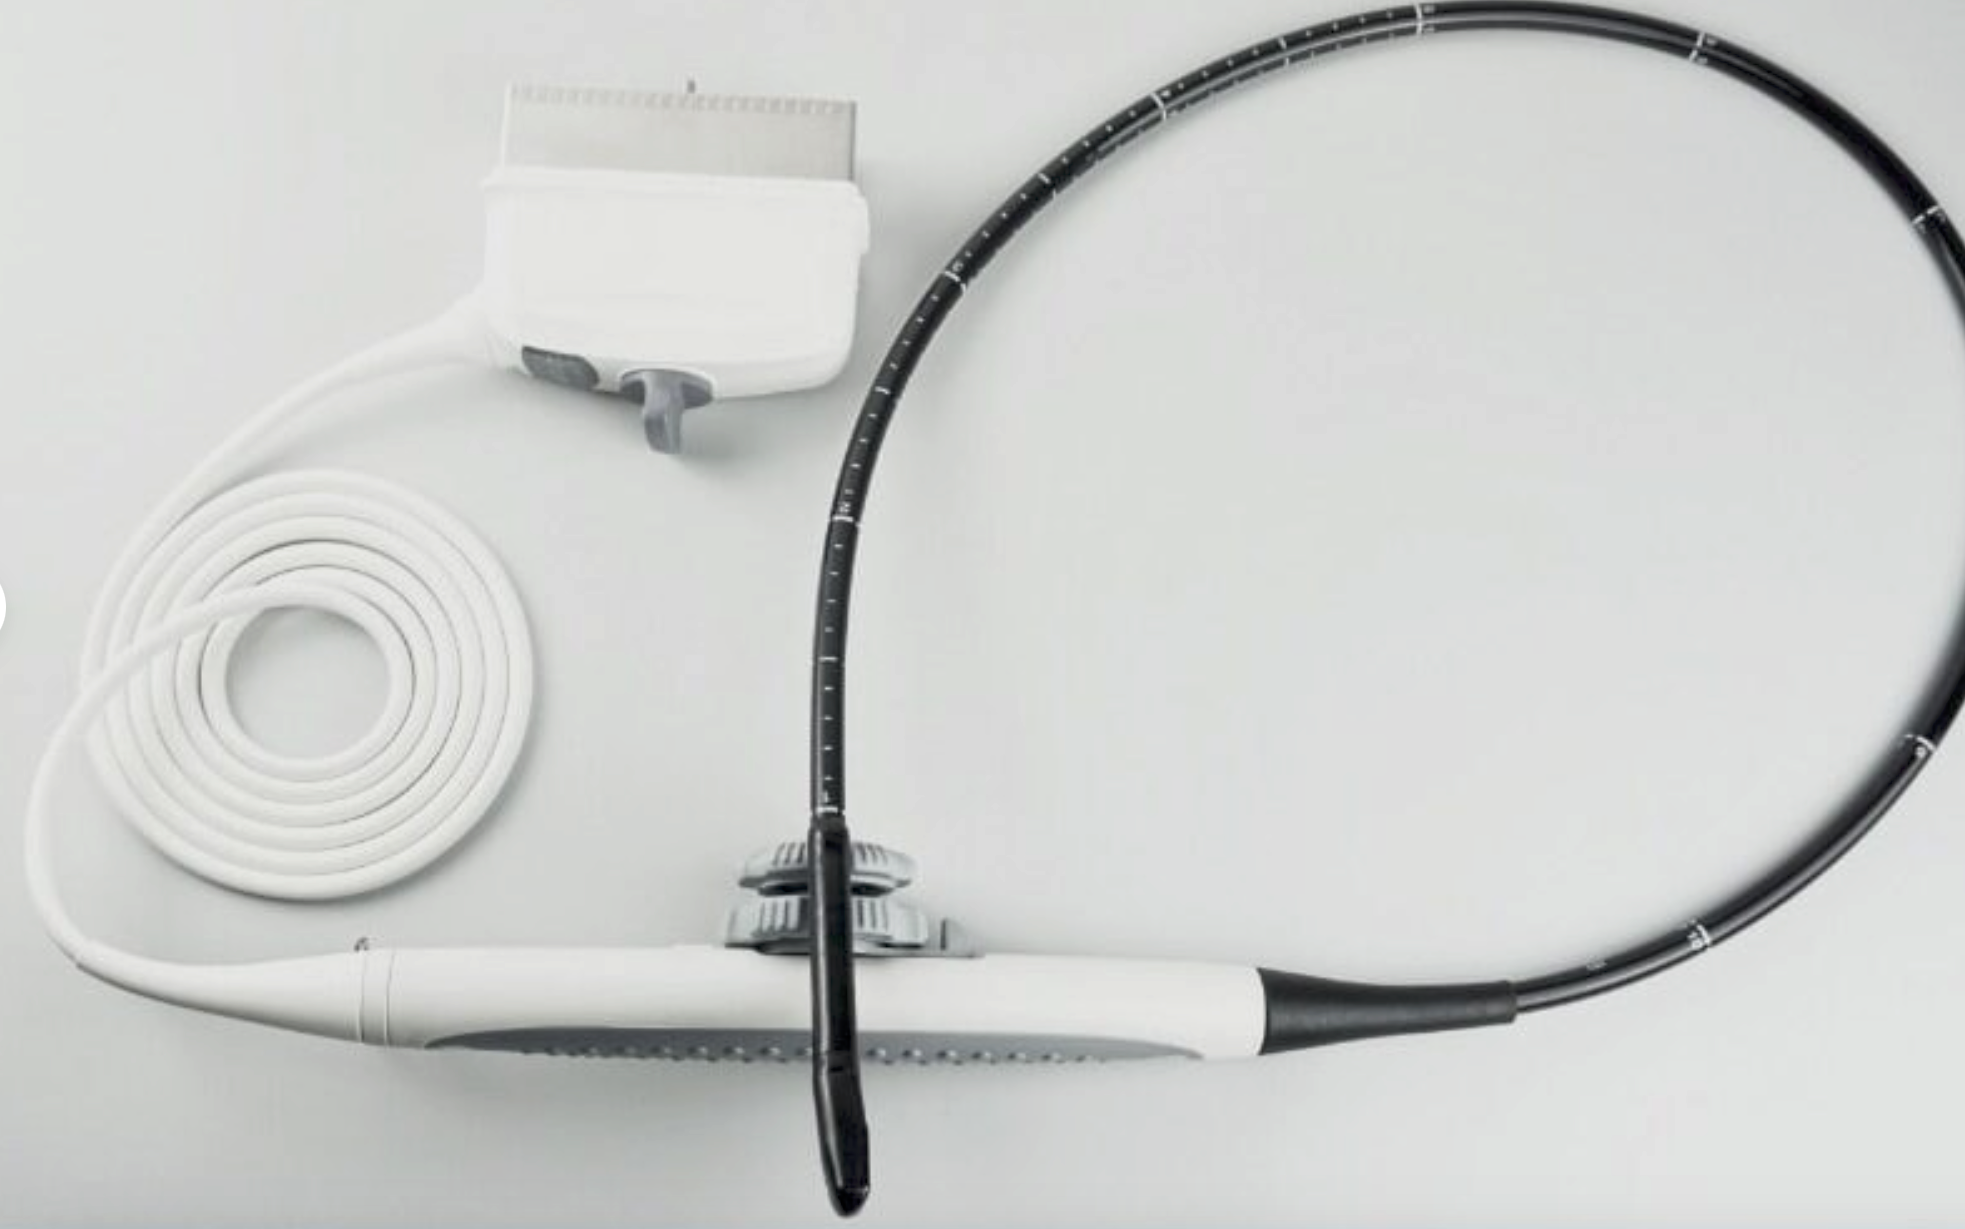

The system typically comes with a probe that is specifically designed to provide clear imaging of the animal’s reproductive organs, allowing the veterinarian to determine the pregnancy status, number of fetuses, and their development stages. With real-time imaging and high-resolution capabilities, it helps in assessing the health of the fetus and identifying potential complications. The machine is lightweight and portable, making it easy to use on farms or in field environments. This ultrasound system is a valuable tool for ensuring the health and wellbeing of pregnant animals and managing breeding programs efficiently.